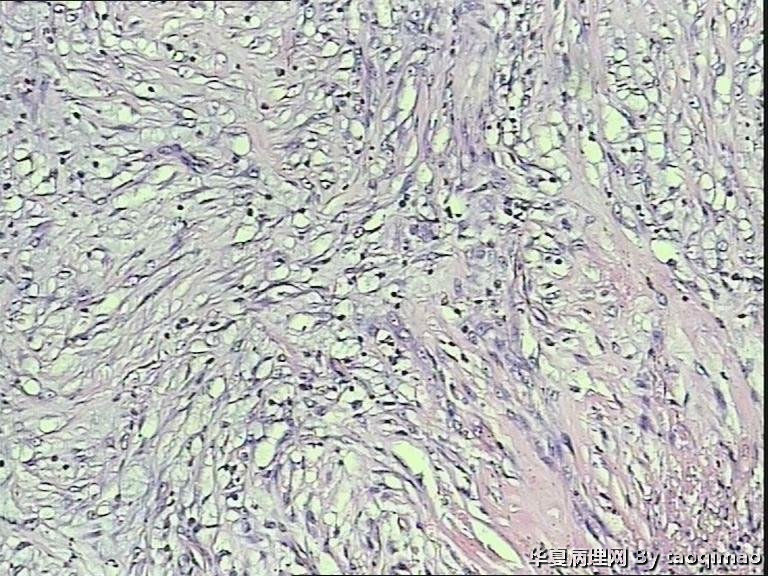

• 胃溃疡?图1

补取的组织

79岁女,胃溃疡,切除胃大部分,与脾有粘连,胃小弯侧可见一溃疡3x2.5x2cm,并且局部胃粘膜增厚,呈皮革胃样外观,切面灰白似粘液样。

肉眼看很像是粘液水汪汪的,很疑惑。

巨大溃疡临床诊断,可是看了间质很浆糊,希望老师们给指点些

胃溃疡,黏液变,没看到明确的上皮样细胞